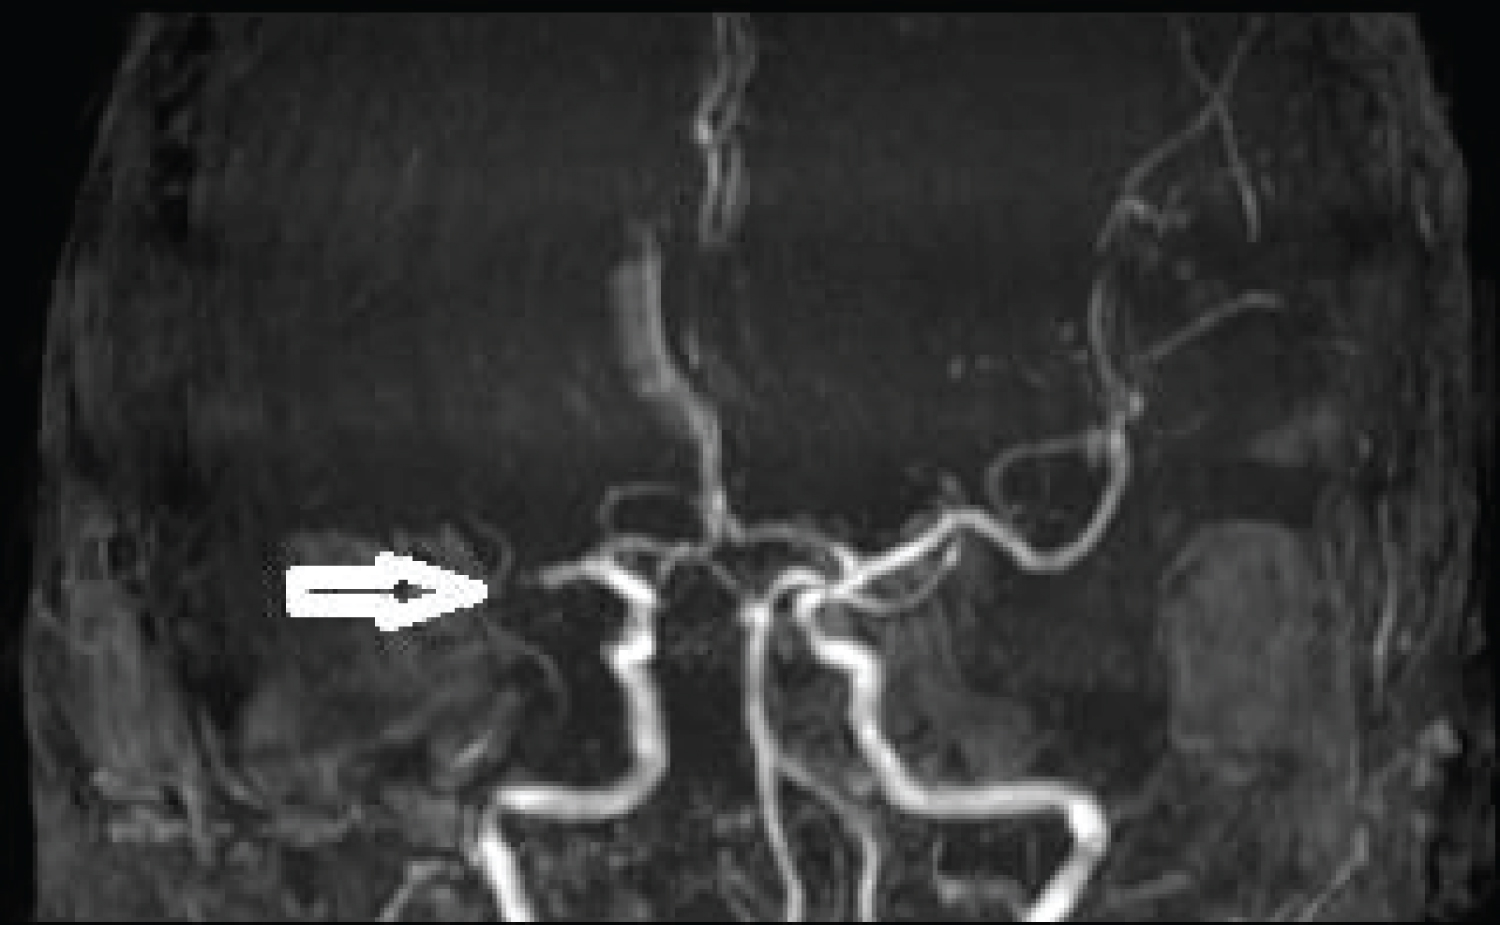

MRI brain done immediately showed patchy diffusion restriction in whole of the right middle cerebral artery (MCA) territory, however, only minimal insular involvement was seen on FLAIR sequence. Thus there was diffusion and FLAIR mismatch. MRA showed complete cut off at proximal right MCA consistent with large vessel occlusion (LVO) (Figure 1 and Figure 2).

Figure 2: Non-contrast MRA showing complete cut off of right MCA. View Figure Chart 2